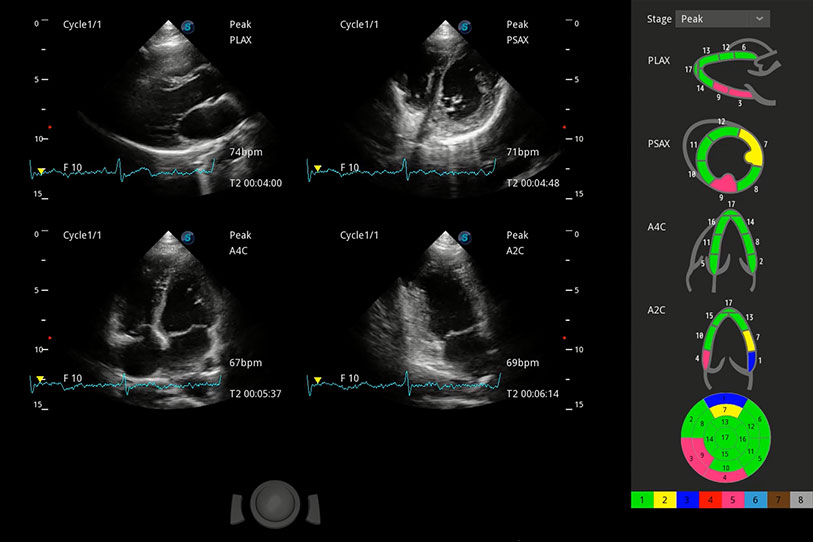

具備多種協(xié)議可選,同時支持17階段劃分法和專業(yè)的SE報告。